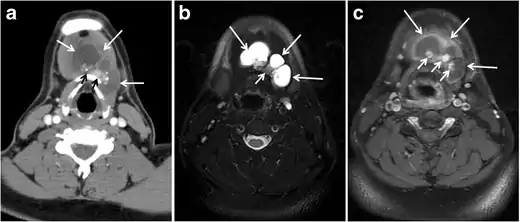

Fig. 8. A 48-year-old male patient post total thyroidectomy with PTC recurrence. a Transverse greyscale ultrasound of the neck demonstrates a left thyroid bed heterogeneous, predominantly hypoechoic irregular lesion with calcifications (white arrow). b A spot image of iodine 123 total body scan of the neck demonstrate a focus of abnormal radiotracer uptake at the left thyroid bed (Black arrows) between the annotated markers. c Enhanced axial CT scan of the neck demonstrates an enhancing large left thyroid bed mass (white arrow) with no calcifications. The lesion exerts a mass effect on the oesophagus (black arrow) and is inseparable from the trachea.[1]